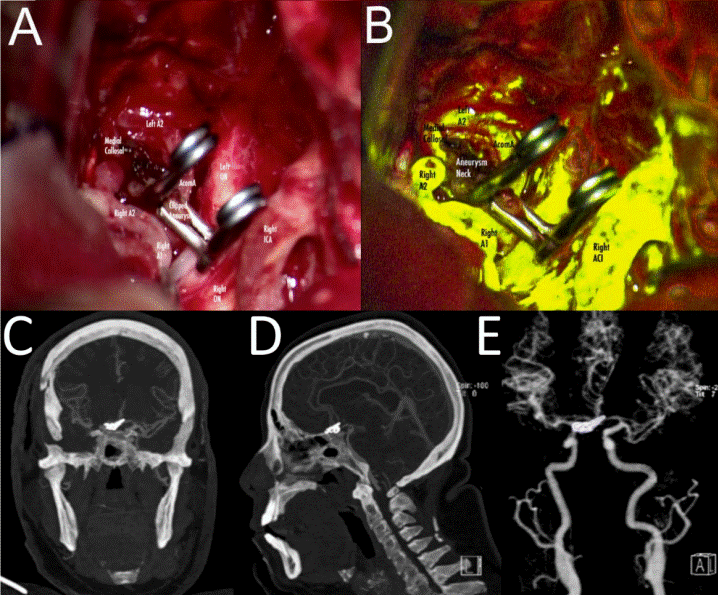

Urgent surgery with standard pterional approach was performed, followed by a sub-frontal corridor and posterior depletion of the carotid and optic-carotid cisterns. Optical nerves, chiasm, carotid artery, and ACA were identified. Opening of the lamina terminalis was performed to achieve brain relaxation. A1 was identified and followed toward the AComA. An anterior-inferior bi-lobulated projecting aneurysm was identified. Dissection of the aneurysm dome was done with bipolar forceps and aspirator. We identified both the infracallosal (A2) arteries; a third artery arising from the AComA was also identified. After the correct identification of all the AComA complex arteries, definitive clipping was performed with a 9 mm straight clip. Fluorescein was administered in a 4 mg/kg dose to confirm parent vessel patency and total aneurysm occlusion. When exposing both A2, a median callosal artery was detected partially occluded by the clip, which made it necessary to relocate it. Aneurysm residual was found in the inferior portion, and a second definitive 5 mm straight clip was used with no residual after clipping. Dural watertight reconstruction, bone repositioning, and aponeurotic repair were performed in the usual manner (Figure 2).

Figure 2 Transoperative photograph and postoperative CT angiography. A. Transoperative photograph showing the AComA complex and the final clip display with no residual. B. Intraoperative fluorescein angiography control with complete patency of the AComA complex and no residual filling of the aneurismal dome. C, D. CT angiography in coronal and sagittal projections displaying clipped AComA aneurysm with a superior projecting dome without residual, and a patent AComA complex with median callosal artery. E. 3D reconstruction of CT angiography showing clip configuration. A1: precommunicating segment; A2: infracallosal segment; Ml: sphenoidal segment; ICA: internal carotid artery; ON: optic nerve; AcomA: anterior communicating artery. CT: computerized tomography; 3D: three-dimensional.

A postoperative CT- angiography (Figure 2) confirmed total occlusion of the aneurysm neck with no residual. The patient evolved satisfactorily with no vasospasm during follow-up and was discharged after six days.